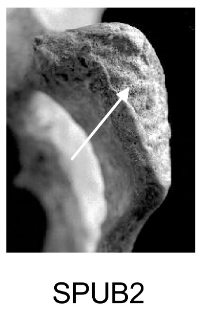

Demi-face antérieure (SPUB)

Changements morphologiques de la demi-face antérieure liés à la formation du rempart ventral.